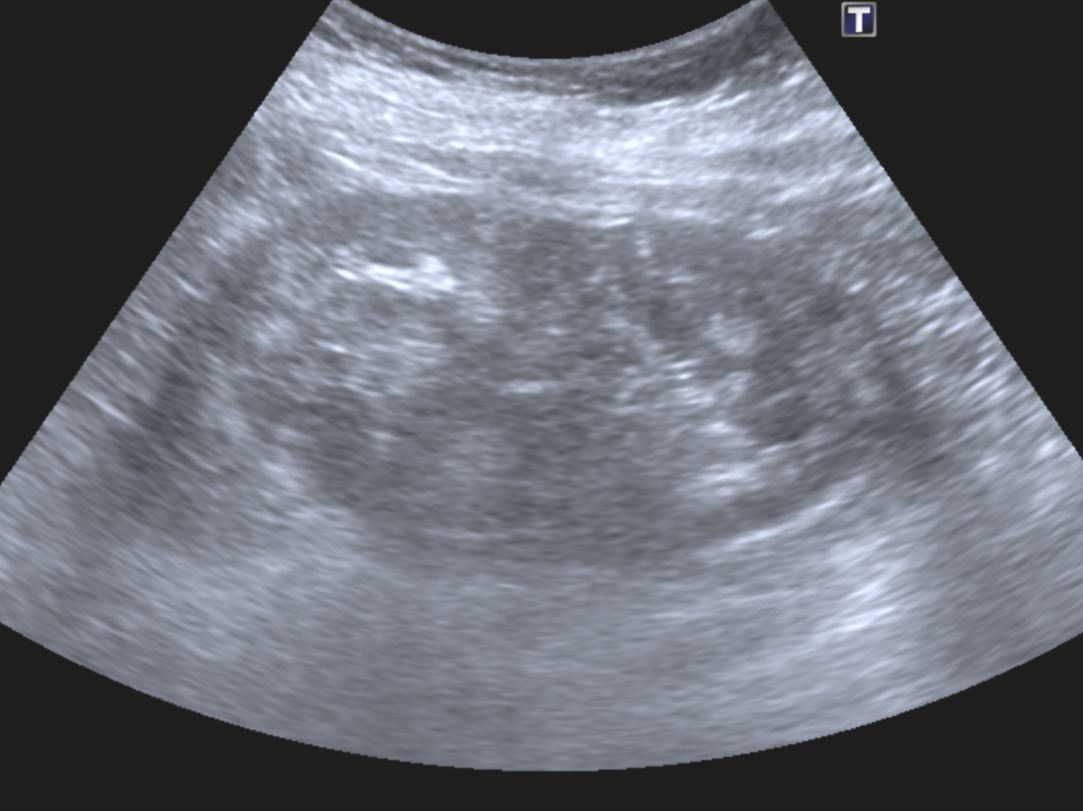

A 45 year old female patient was referred by her GP for a renal ultrasound to investigate hypertension resistant to drug treatment. She was otherwise in good health and had no previous medical history of note or relevant family history. Representative ultrasound images of the kidneys are shown in Figures 1 and 2.